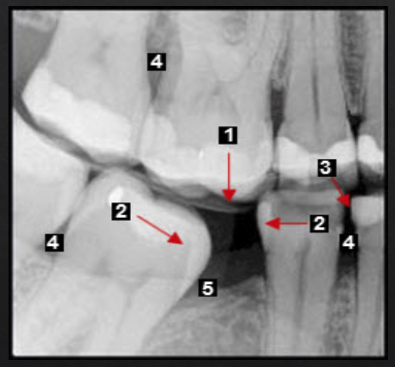

Posterior bite collapse as a result of 1st molar extraction demonstrates multiple occlusal issues that may result in periodontal problems such as

Super-eruption, resulting in root and furcation exposure

Molar tipping, creating a pseudopocket (5)

Open contact, a risk factor for food impaction and gingival inflammation (4)